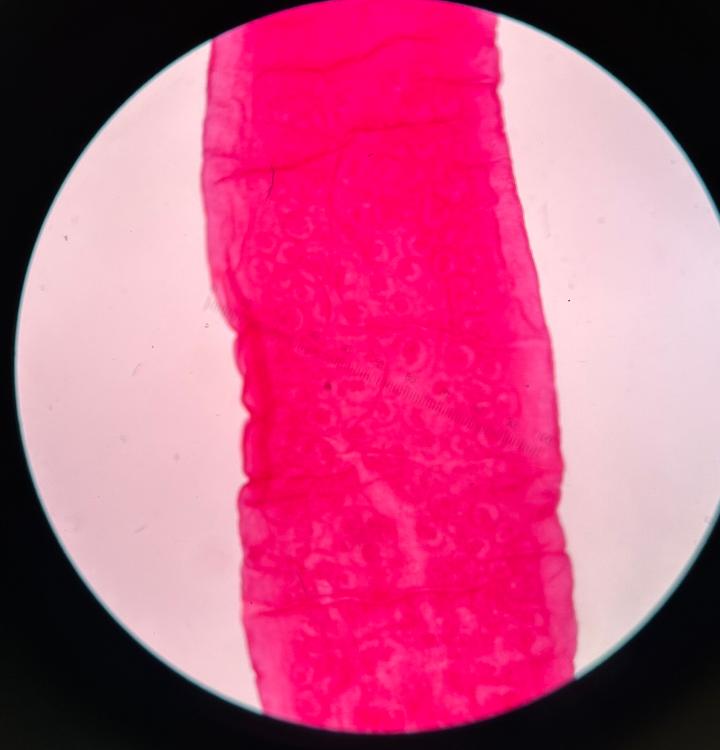

Trichinella (muscle section)